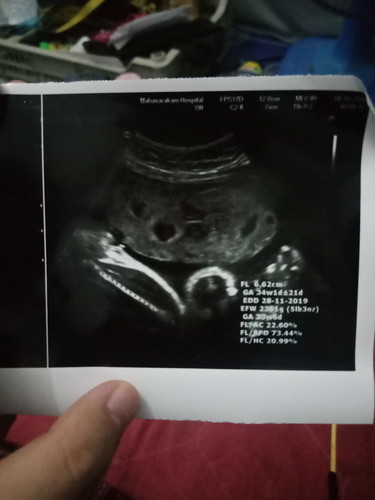

วันนี้ไปซาวมา มีตรงไหนที่บอกน้ำหนักลูกบ้างมั้ยค่ะ